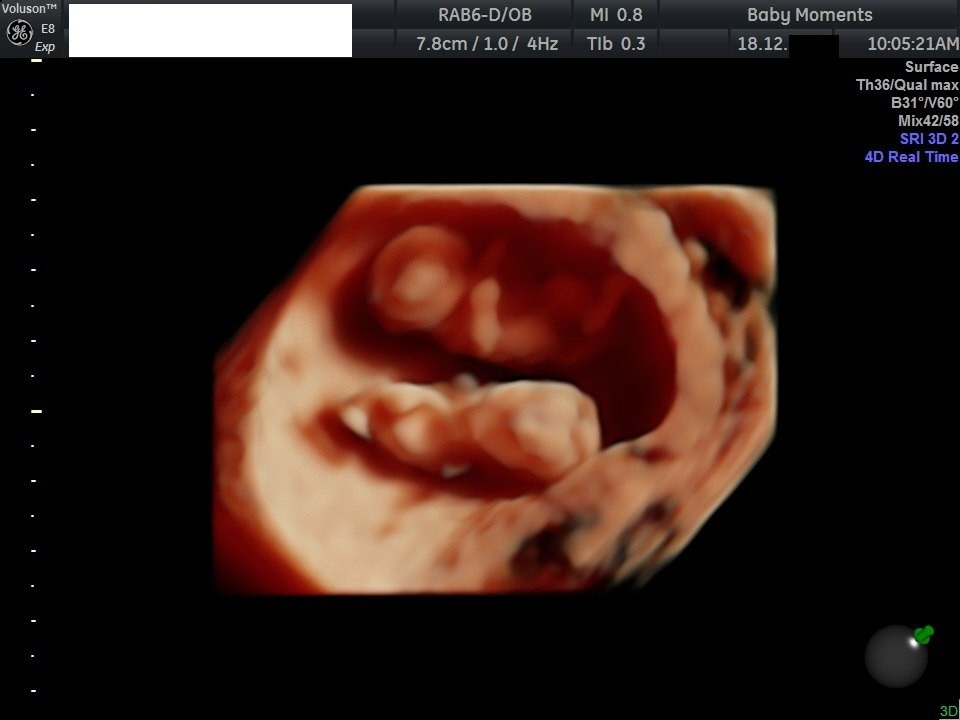

4D Baby Scan in Oxfordshire – See Your Baby in Stunning Detail Baby moments

Experience the magic of seeing your baby move, yawn, stretch, and smile before birth with our 4D Baby Ultrasound Scan in Oxfordshire. Using the latest high-definition 4D imaging technology, we bring your baby’s world to life in real-time — creating a truly unforgettable bonding experience for parents and families. baby Scan, 4D baby Scan

At our Oxfordshire ultrasound clinic, our experienced sonographers provide a safe, comfortable, and welcoming environment for every expectant parent. Whether it’s your first baby or a new addition to your growing family, our 4D baby scan offers a heartwarming glimpse into your little one’s world.

We recommend booking your 4D scan between 24 and 32 weeks of pregnancy. During this time, your baby’s features are beautifully developed, and you’ll be able to see detailed, moving images in real-time.